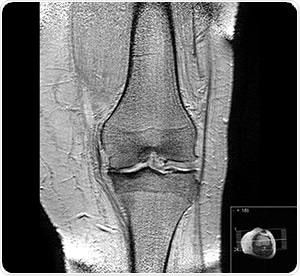

Knee osteoarthritis stages II and III by Harrygouvas at Greek Wikipedia. [CC BY-SA 3.0 or GFDL 1.3], from Wikimedia Commons

Osteoarthritis is a common degenerative condition. It is characterized by the diminution of cartilage in and around the joints which results in pain and loss of mobility. Age is seen to be the most common cause of osteoarthritis, but, traumatic joint injury can also cause joint degeneration in people of all ages. The progression of the condition can be slowed and symptoms can certainly be managed, however the underlying causes that lead to the development of this condition cannot be reversed.

Recent studies on osteoarthritis have led to the belief that changes to the subchondral (below the cartilage) bone structures, like thickening of the subchondral plate, are apparent prior to lesions or other symptoms becoming obvious in the cartilage itself.

The current standards giving recommendations on the diagnosis and treatment of osteoarthritis depend on radiographic imaging to detect either of two things. First, the hardening of the subchondral layer, or second, a reduction in joint space and visual and tactile inspection during arthroscopic surgery.